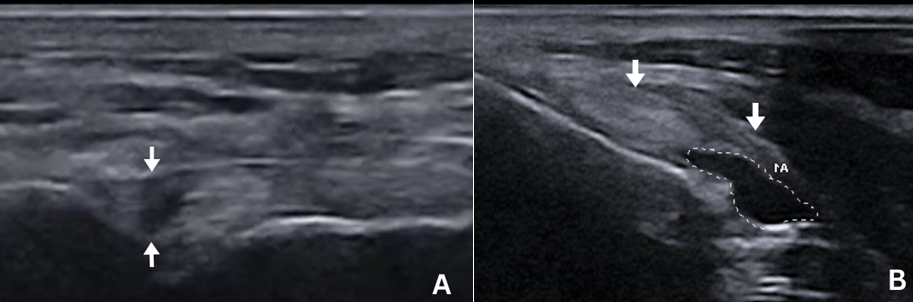

Case of the Month Featured Jan 9, 2025 Suspected Renal Dysplasia in a young dog Jan 9, 2025 Sonographer: Meredith Adams, DVM Jan 9, 2025 Dec 5, 2024 Incidental Abdominal Mass Dec 5, 2024 Sonographer: Emily Evans, DVM Dec 5, 2024 Nov 1, 2024 Ultra Rare Pancreatic Disease in Cats Nov 1, 2024 Sonographer: Mallory Repellin DVM Nov 1, 2024 Oct 8, 2024 Suspected Carcinomatosis in a Feline Oct 8, 2024 Sonographer: Kara Woody DVM Oct 8, 2024 Sep 19, 2024 Lameness in a Dog Sep 19, 2024 Sonographer: Anne Desrochers DACVIM Sep 19, 2024 Jul 31, 2024 Ruff Findings: Uncovering a Rib Mass in a Juvenile Dog Jul 31, 2024 Sonographer: Danny Laderberg DVM Jul 31, 2024 Jul 3, 2024 Thyroid Carcinoma in a Canine Jul 3, 2024 Sonographer: Meredith Adams DVM Jul 3, 2024 May 30, 2024 Pituitary Dependent and Adrenal Dependent Hyperadrenocorticism in Two Littermates May 30, 2024 Sonographer: Emily Evans BVM&S May 30, 2024 May 1, 2024 Gastrointestinal Adenocarcinomas in a Feline May 1, 2024 Sonographer: Mallory Repellin DVM May 1, 2024 Mar 27, 2024 March’s Case of the Month - 2024 Mar 27, 2024 Sonographer: Kara Woody DVM Mar 27, 2024 Feb 28, 2024 February's Case of the Month- 2024 Feb 28, 2024 Sonographer: Anne Desrochers, DACVIM Feb 28, 2024 Feb 1, 2024 January's Case of the Month-2024 Feb 1, 2024 Sonographer: Danny Laderberg, DVM Feb 1, 2024 Dec 28, 2023 December’s Case of the Month-2023 Dec 28, 2023 Sonographer: Meredith Adams, DVM Dec 28, 2023 Nov 30, 2023 Novembers Case of the Month-2023. Nov 30, 2023 Sonographer: Emily Evans DVM Nov 30, 2023 Nov 1, 2023 October's Case of the Month - 2023 Nov 1, 2023 Sonographer: Mallory Repellin DVM Nov 1, 2023 Sep 27, 2023 September's Case of the Month - 2023 Sep 27, 2023 Sonographer: Kara Woody DVM Sep 27, 2023 Aug 30, 2023 August's Case of the Month - 2023 Aug 30, 2023 Sonographer: Anne Desrochers DACVIM Aug 30, 2023 Aug 3, 2023 July's Case of the Month - 2023 Aug 3, 2023 Sonographer: Meredith Adams, DVM Aug 3, 2023 Jul 6, 2023 June's Case of the Month! Jul 6, 2023 Sonographer: Emily Evans, BVM&S Jul 6, 2023 Jun 7, 2023 May's Case of the Month - 2023 Jun 7, 2023 Sonographer: Mallory Repellin, DVM Jun 7, 2023 Apr 26, 2023 April's Case of the Month - 2023 Apr 26, 2023 Sonographer: Kara Woody, DVM Apr 26, 2023 Mar 29, 2023 March's Case of the Month - 2023 Mar 29, 2023 Sonographer: Anne Desrochers, DACVIM Mar 29, 2023 Mar 1, 2023 February's Case of the Month - 2023 Mar 1, 2023 Sonographer: Meredith Adams, DVM Mar 1, 2023 Feb 1, 2023 January's Case of the Month - 2023 Feb 1, 2023 Sonographer: Dr. Emily Evans Feb 1, 2023